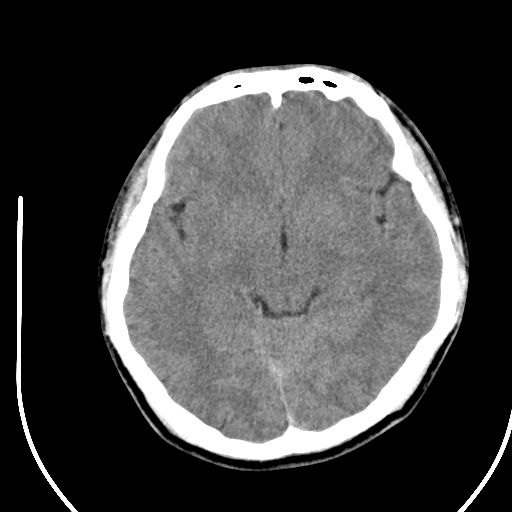

标题: CT28158:男,27Y。头痛数月,左顶叶血管瘤。 [打印本页]

标题: CT28158:男,27Y。头痛数月,左顶叶血管瘤。

海绵状血管瘤

考虑左顶叶海绵状血管瘤,建议mr检查。

左侧额叶海绵状血管瘤可能性大;建议行mri检查。

考虑血管畸形,因其周可见水肿,不除外感染性病灶。建议mri检查。